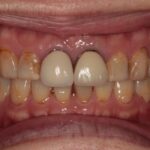

ダイレクトボンディングなどの

審美治療も高精度に対応

肉眼では見えない細かな部分まで拡大して確認できるため、削りすぎを防ぎ、再発リスクを抑えた質の高い治療が可能です。

当院では、カリーナシステムを活用し、治療前・治療中・治療後の状態を静止画や動画で記録。実際の映像を一緒に見ながら、分かりやすく丁寧にご説明します。